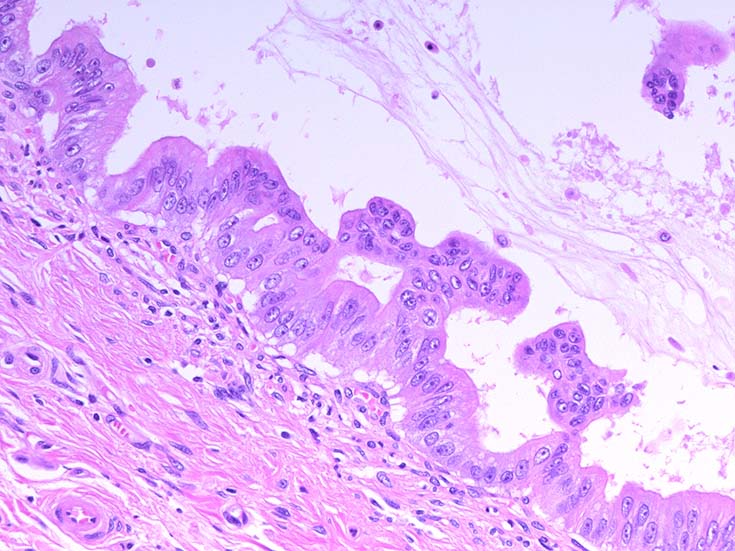

膵上皮内腫瘍性病変 pancreatic intraductal neoplasm(PanIN)*16

Low-grade PanINとhigh-grade PanINの分類

high-grade PanIN

PanINの図譜はJohns Hopkins The Sol Goldman Pancreatic Cancer Research CenterのHome page*19から引用.

2. PanIN-2, PanIN-3;

• TP53の不活化--PanINでのIHCでは機能喪失が,PanIN3のみで観察される. 膵癌発がん過程の遅い段階に出現する事象.

浸潤性膵癌では, 50-75%で不活化.

• SMAD4の不活化--PanIN3の30%で発現陰性化. PanIN-1,2では, SMAD4免疫染色は陽性. 発現の陰性化は後期PanINで発現する重要な異常*20.

浸潤性膵管癌では, 55%で不活化.

• BRCA2(DNA修復に重要な遺伝子)の不活化--PanINではPanIN3に特異的なイベント. germ line変異は浸潤性膵管癌の7~10%に認められる.

• cyclinD1過剰発現--PanIN1ではまれ, PanIN-2では29%, PanIN-3では57%と膵癌発がん過程に伴って頻度が上昇する遺伝子変化.

• COX-2の過剰発現--悪性腫瘍では, 細胞増殖, 生存, 浸潤および, 血管新生に関与. 正常膵管,PanIN-1では発現が低く, PanIN2から過剰発現頻度が高くなる.